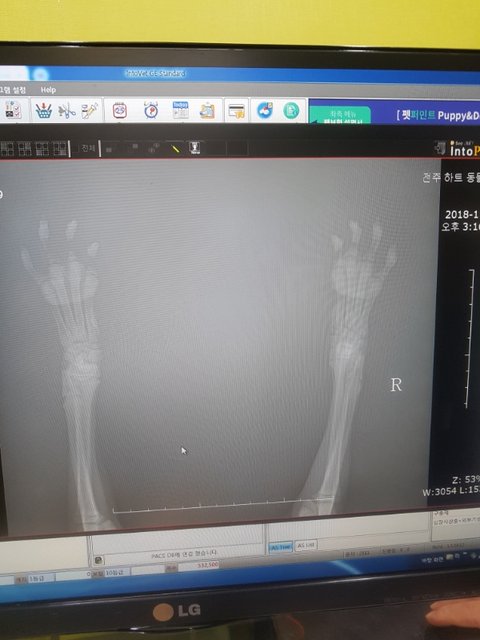

검진 다녀왔습니다

다행히 골절은 아니라고 합니다.

영양실조..

영양부족으로 구루병이 생긴듯 하다고 하시네요